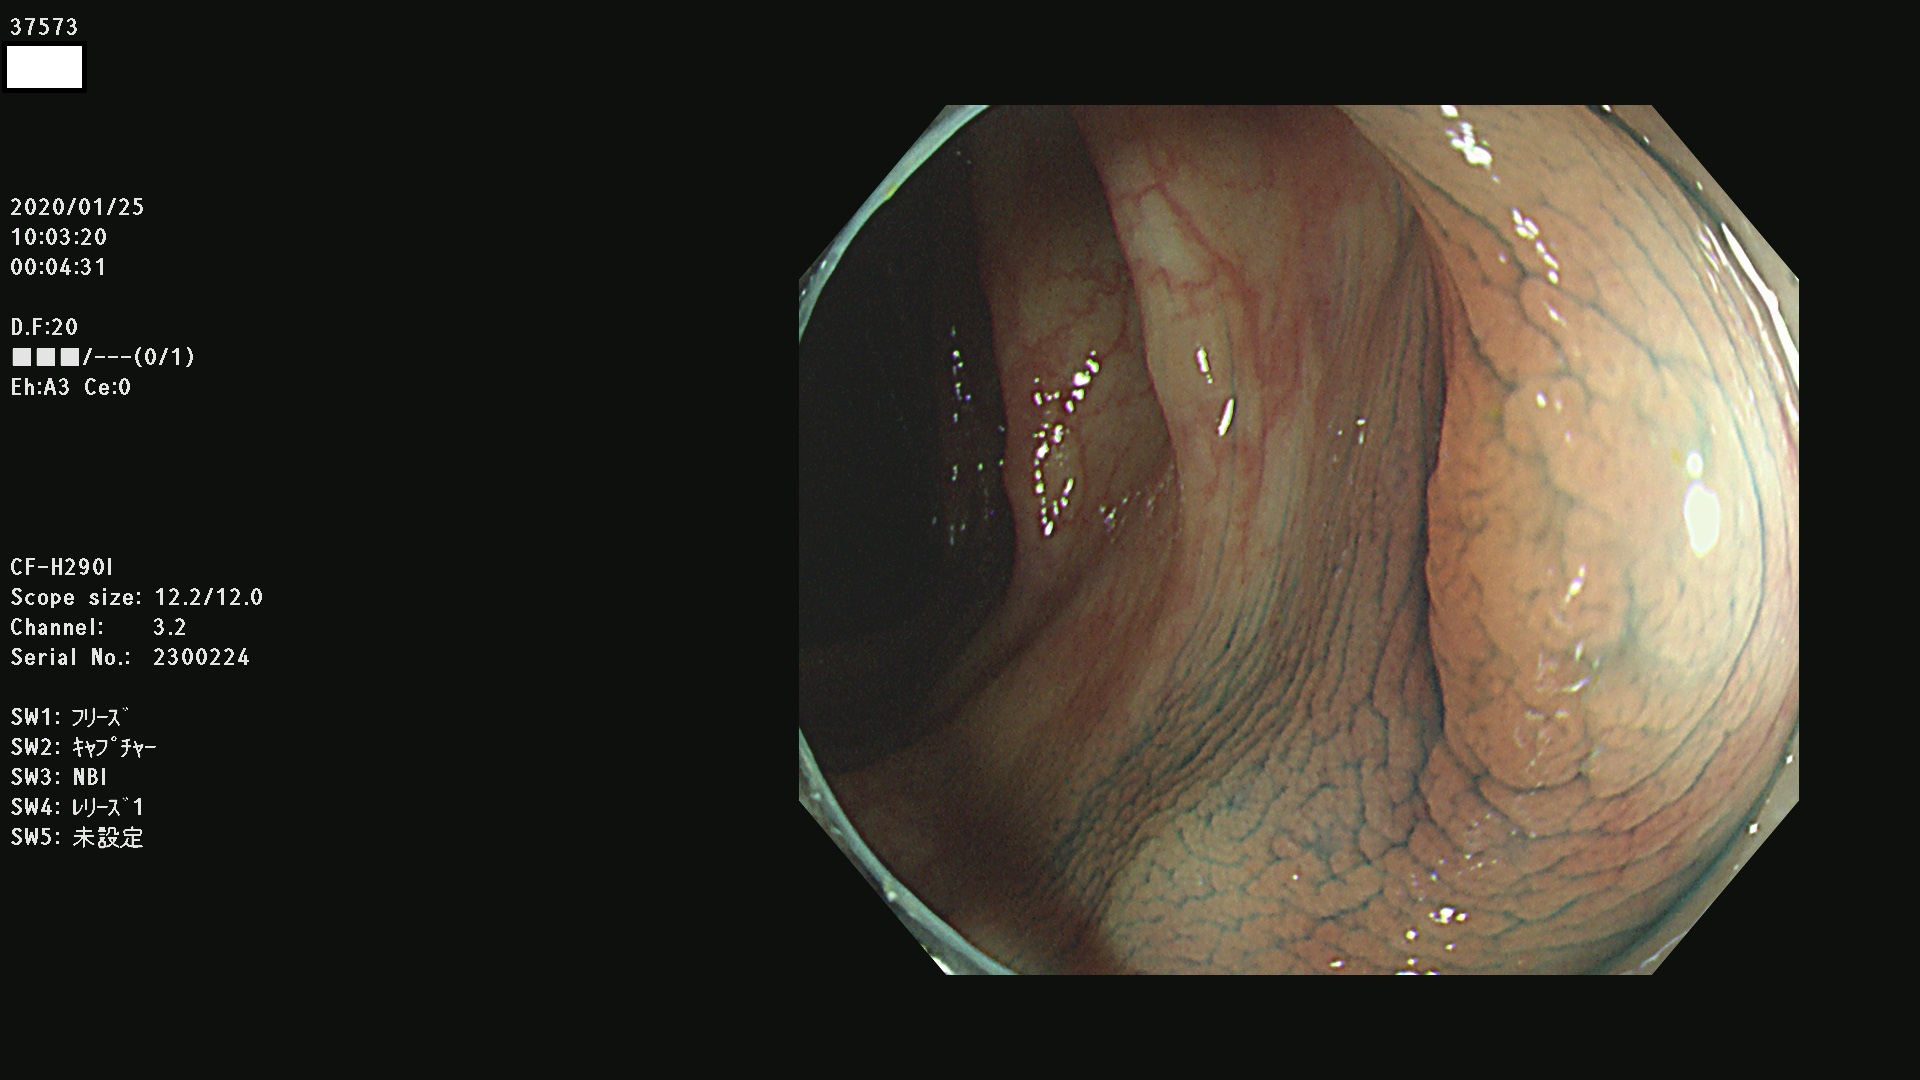

発見困難で危険性の高い平坦型病変(上記100名より抽出) ![]()